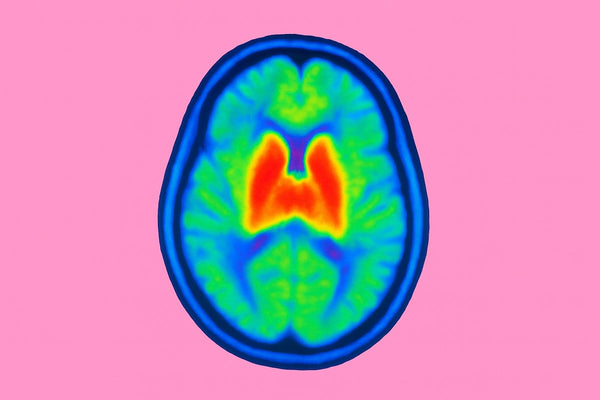

Close-up of a physician in a white coat with a stethoscope, representing natural brain and mood regulation support.

A Doctor’s Guide to Supporting Brain & Mood Regulation Naturally

Brain and mood regulation are often discussed as abstract ideas—something we either possess or struggle with, depending on stress, genetics, or lif...